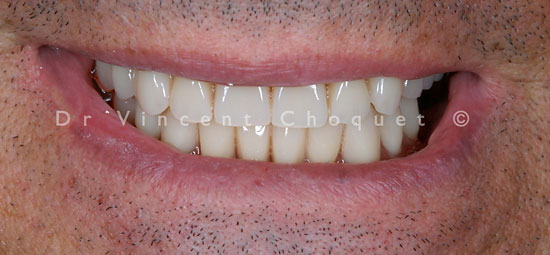

Cas Cliniques Avant et Après

Cas 1 : Esthétique Dentaire

Cas 2 : Esthétique Dentaire

Cas 3 : Esthétique Dentaire

Cas 4 : Esthétique Dentaire

Cas 5 : Esthétique Dentaire

Cas 6 : Esthétique Dentaire

Cas 7 : Esthétique Dentaire

Cas 8 : Esthétique Dentaire

Cas 9 : Esthétique Dentaire

Cas 10 : Esthétique Dentaire

Cas 11 : Esthétique Dentaire